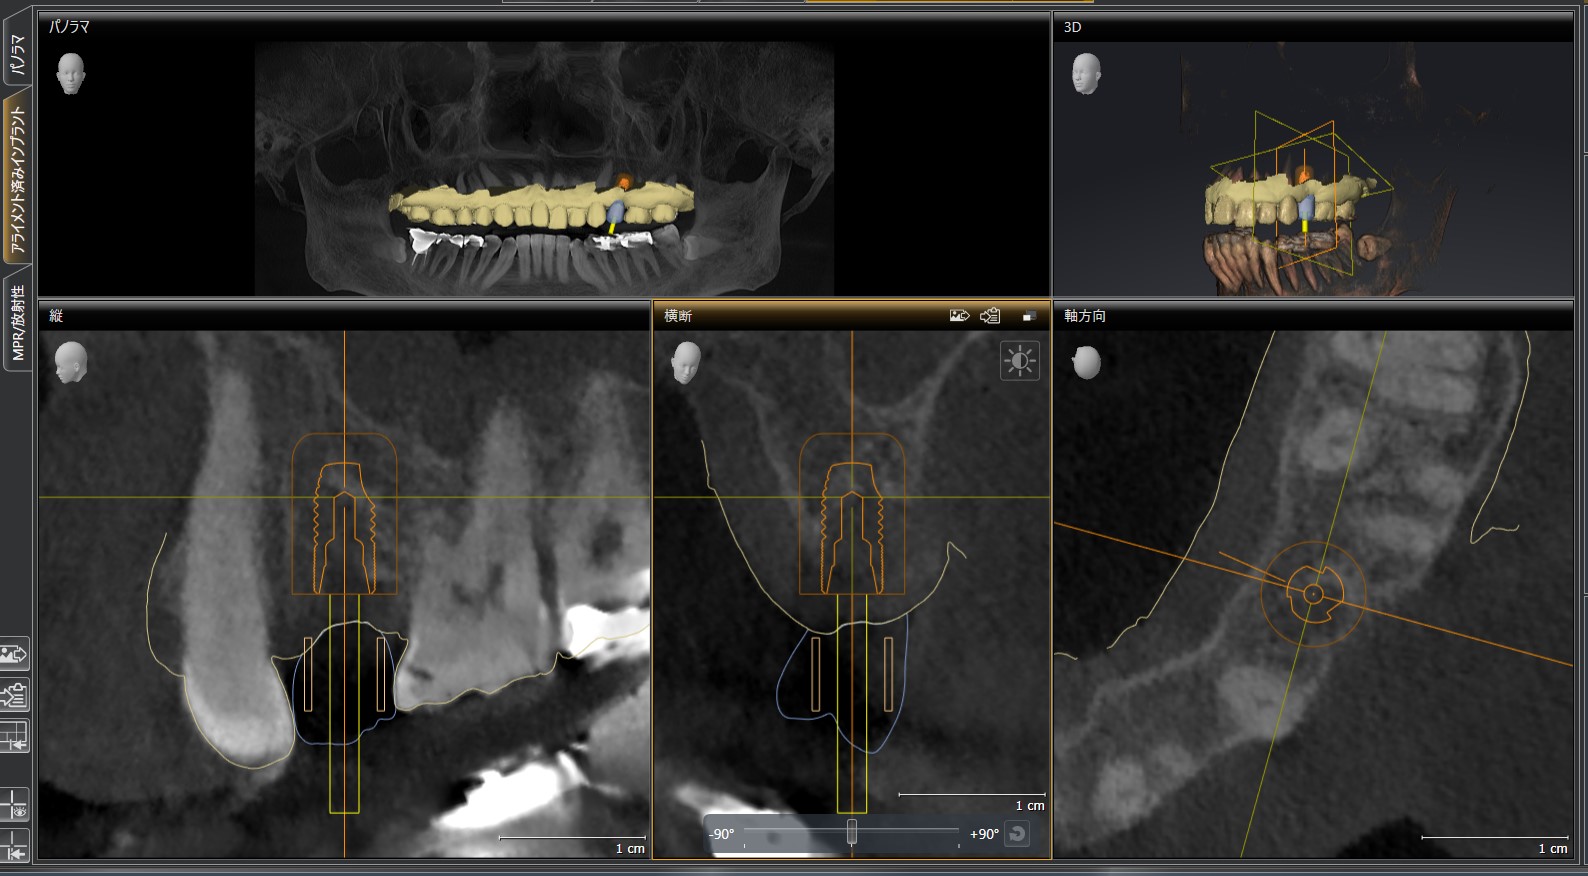

CT画像

| 主訴 | 左上の歯が欠けている |

| 治療内容 |

左上5番 |

| 治療期間 | 約6ヶ月 |

| 治療費用 |

672,000円(税込) |